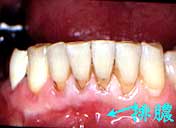

40歳・女性

10年間骨吸収はほとんど停止、喪失歯もなく経過良好

口腔清掃状態はそれ程悪くはないが、全体に歯槽骨吸収が著しく、軽度なところで1/3以上、 著明なところは1/2以上吸収しており、40歳という年齢を考えると将来は悲観的。

75|は抜髄の上、歯周外科処置(FOp+HAP)を行い、それ以外の部位については、 P-cur と毎月のプロフェッショナル・トゥースクリーニングを行い経過観察することとした。 初診より5年を経過した頃より|6の知覚過敏を訴えるようになり、薬物塗布により鎮静 に努めたが、最終的には歯髄壊疽により根管治療を行った。

治療の時に悲観的だった7|6は、それぞれ動揺と軽度な咬合痛が消失しないまま 長期にわたり機能し続けている。

一方着目すべきは、それ以外の歯が10年後も初診時と変わらず、あたかも骨吸収進行が停止 したかのように思える点である。

初診時(40歳)までの歯槽骨吸収速度と、メインテナンスを始めてから10年間の進行速度が 明らかに違う。P-cur と毎月のプロフェッショナル・トゥースクリーニングだけで獲得できた意義 は臨床家として高く評価したい。